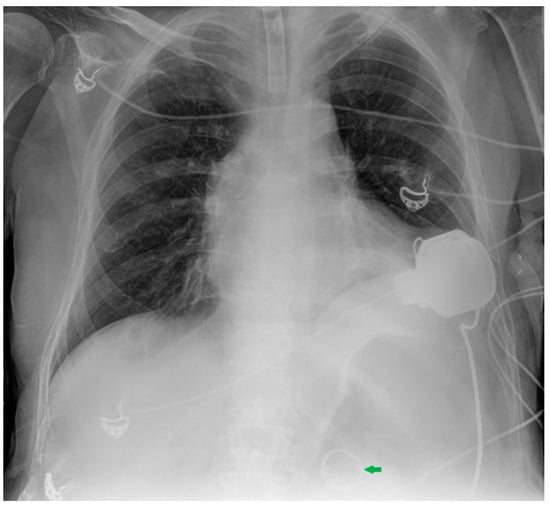

7. Chest Tubes

| Device | Most Frequent CXR-Detectable Anomalies and Complications |

|---|---|

| Chest tubes | Kinking Extrapleural/intrafissural/intraparenchymal/misposition Mediastinum juxtaposition Diaphragmatic trespassing Mediastinal invasion (uncommon) |